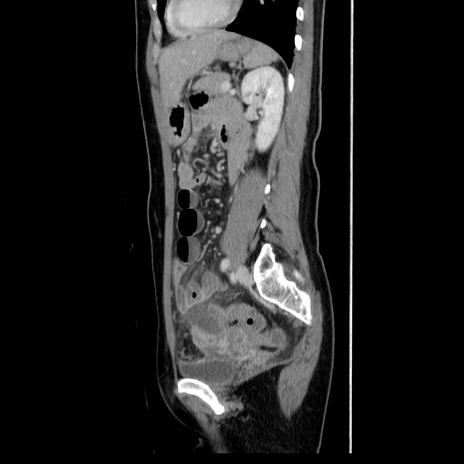

症例39(矢状断像)

【症例】40歳代女性

【主訴】上下腹部痛

【現病歴】2日目から下腹部痛あり。夜間は痛みで眠れなかった。昨日より上腹部痛と下痢が出現。臥位で痛みは軽快したため、休んでいた。本日になって臥位でも立位でも痛みが強くなってきたため救急要請。

【既往歴】子宮内膜症

【身体所見】部:平坦・軟、左上下腹部に圧痛あり、反跳痛あり。

【データ】WBC 21800、CRP 26.78

CT